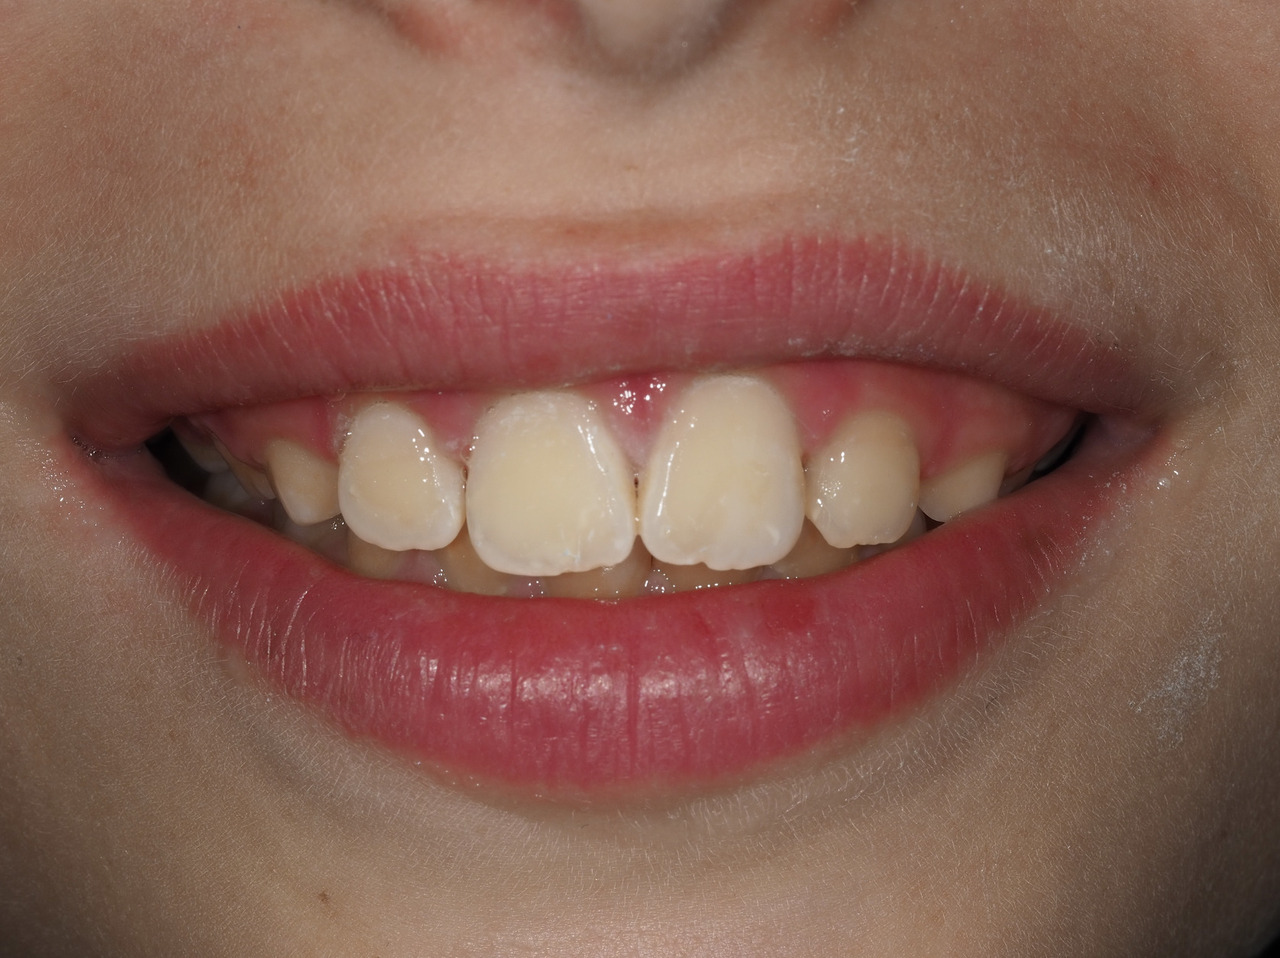

Le diagnostic repose sur l’observation clinique : des opacités (taches) blanches, beiges ou brunes de taille variable sont présentes et visibles sur les dents atteintes (fig. 1, 2 et 3). Les opacités, bien démarquées, sont présentes dès l’éruption de la dent et leur taille ne se modifie pas dans le temps. Cependant, l’émail étant plus fragile, des fractures amélaires post-éruptives sont observées, entraînant des pertes de substance surtout au niveau des molaires qui sont soumises aux forces de mastication. L’atteinte est asymétrique, c’est-à-dire que pour un même patient sa sévérité peut varier d’une dent à l’autre, allant d’une absence d’atteinte à une perte de substance importante, en passant par une dyschromie discrète. Si une tache est observée sur une incisive permanente, il est important d’examiner les molaires permanentes. Le médecin généraliste doit alors évoquer une anomalie de structure dentaire et orienter le patient vers un chirurgien-dentiste. Celui-ci confirmera le diagnostic de MIH ou établira un autre diagnostic. Les diagnostics différentiels sont :

Les dents antérieures ont rarement des pertes de substance ou des lésions carieuses ; la problématique réside dans l’aspect disgracieux des lésions (fig. 3). Pour la gestion de ces taches, des traitements plus ou moins invasifs pourront être envisagés seulement pour des enfants avec une bonne hygiène bucco-dentaire et une coopération suffisante : micro, macro-abrasion, ou infiltration résineuse.9 Ils sont utilisés seuls ou en combinaison et nécessitent parfois la réalisation d’une restauration collée en résine composite (fig. 4).